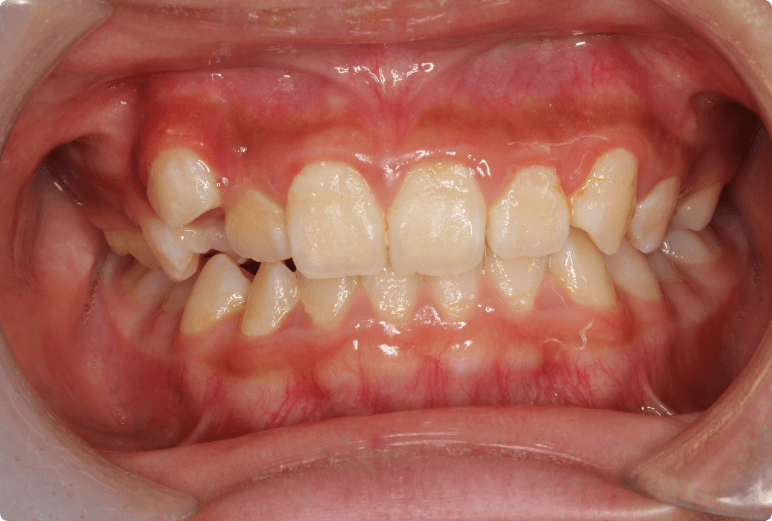

八重歯を改善した症例

BEFORE

症例概要

年代、性別

12歳 女の子(成人と同様の矯正治療)

主訴

八重歯

診断

骨格性Ⅰ級、歯性Ⅱ級、前歯部叢生

治療内容

上顎左右4番抜歯、唇側ワイヤー矯正、リテーナー

治療期間

2年+メンテナンス

治療リスク

痛み、歯根吸収、歯肉退縮

治療費用

990,000円(税込)